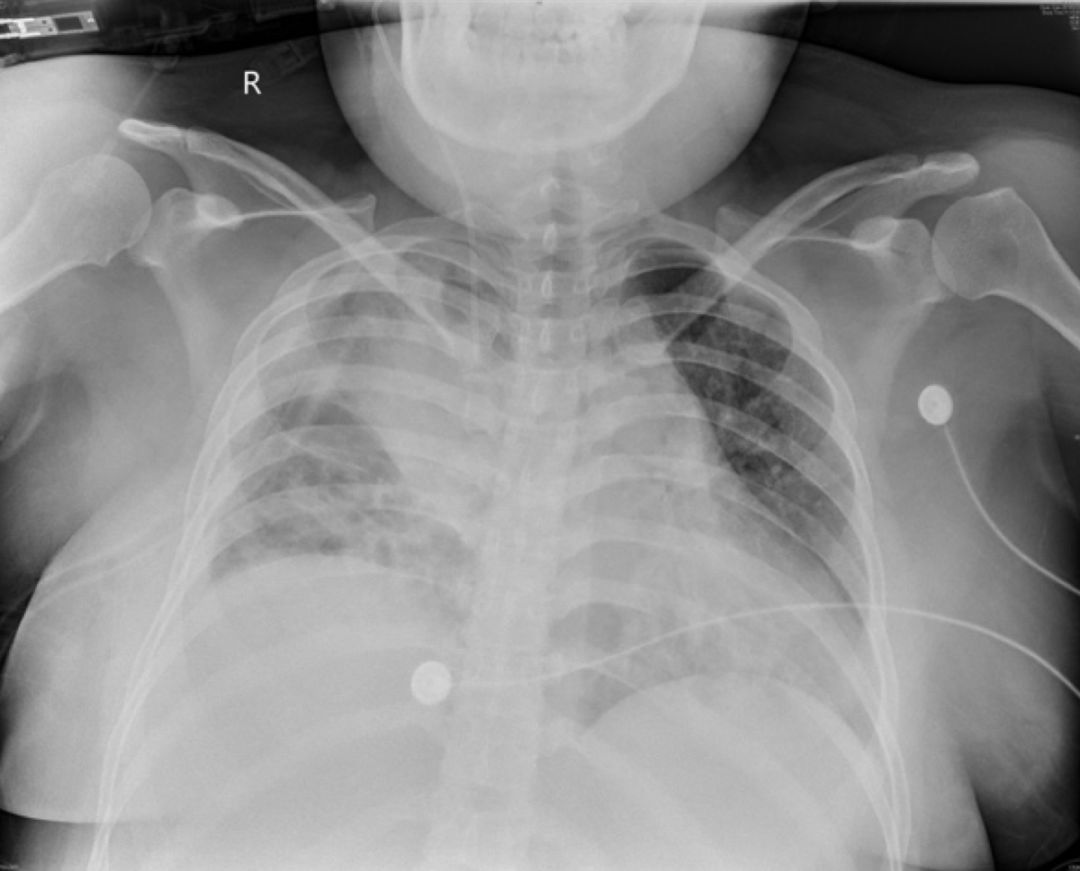

2019-5-13我院胸片

患者青年女性,因「咳嗽、咳痰、咯血半月余,胸痛8天」入院,急性起病,逐渐加重,胸部CT提示右侧气胸,双肺相对弥漫分布的气囊与结节,沿气管血管束分布,右下肺实变。肺部弥漫性囊泡样疾病,需要考虑肺淋巴管平滑肌瘤病(LAM)、BHD综合征、肺朗格汉斯组织细胞增生症(PLCH)、淋巴细胞性间质性肺炎(LIP)、感染性疾病如耶氏肺孢子菌肺炎(PCP)等疾病。LAM一般常见于育龄期女性,影像学以弥漫均匀分布的薄壁囊泡为主要表现,此例患者为年轻女性,肺部多发囊泡,需要考虑LAM,但囊泡不是薄壁,分布不均匀,形状不规则,不符合LAM的典型表现。PLCH一般多见于吸烟患者,影像学以奇形怪状的沿支气管血管束分布的囊泡样改变为特点,吸烟患者一般以上叶及中叶病变为主,不累及肋膈角,多系统病变患者可以累及肋膈角,本例需考虑PLCH可能。BHD综合征肺部表现为多发薄壁囊肿,形状不规则,多于基底部、外周、沿纵隔分布,其他系统表现可合并皮疹、肾肿瘤等,可有家族史,本例患者无BHD家族史,需进一步排查其他器官有无病变。LIP常有肺部多发囊泡改变,一般合并自身免疫性疾病,该患者需进一步完善自身抗体等风湿免疫相关指标,协助诊断。此外,还需考虑PCP、金葡菌感染等感染性疾病。PCP多见于免疫抑制宿主,可以有多发性肺气囊的表现,该患者无发热,无免疫抑制病史,目*考前**虑可能性不大。